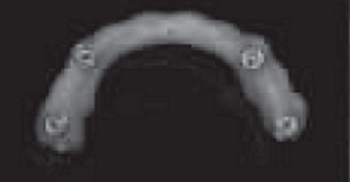

1.2.3治療過程:先行微創(chuàng)拔除14、13、21、22、23、24及25,搔刮拔牙窩去除炎癥組織,常規(guī)制作一副上頜過渡義齒(圖4,5)。2個(gè)月拔牙術(shù)后復(fù)診,利用上頜過渡義齒作為個(gè)性化托盤取上頜模型并翻制石膏模型,在石膏模型上根據(jù)過渡義齒標(biāo)出各個(gè)牙位,同時(shí)利用壓膜機(jī)制作放射性模板(如圖6)?;颊吲宕鞣派湫阅0迮臄z全景片及CBCT(如圖7、8)。

圖6 放射性模板制作

放射性模板是指帶有放射性阻射標(biāo)記物的模板,在患者種植手術(shù)前戴入口內(nèi)并進(jìn)行放射性拍攝,可評估種植位點(diǎn)骨質(zhì)及可用骨量,從而設(shè)計(jì)種植體的數(shù)目、位點(diǎn)及方向,指導(dǎo)最終手術(shù)方案。放射性模板能顯示種植位點(diǎn)或未來修復(fù)體的信息,它的組織面需與其下方的粘膜緊密貼合且在放射性拍攝過程中保持穩(wěn)定位置。本病例首先按照全口修復(fù)計(jì)劃,給患者制作上頜過渡義齒。利用過渡義齒作為個(gè)性化托盤取模翻制石膏模型,并在石膏模型上按照過渡義齒標(biāo)記牙位,繼而使用真空壓膜機(jī)制作樹脂薄膜導(dǎo)板,然后在樹脂導(dǎo)板相應(yīng)牙位打孔并填塞放射性顯影的材料如牙膠?;颊吲鍘Х派湫阅0暹M(jìn)行錐形束CT(CBCT)的掃描,從而得到種植位點(diǎn)骨組織的情況。牙列缺失的患者其放射性模板由粘膜支持,有可能在放射性掃描的過程中移位,可使用咬合記錄進(jìn)行固定。本病例所制作的放射性模板與患者的粘膜較為貼合,有較強(qiáng)的固位力。